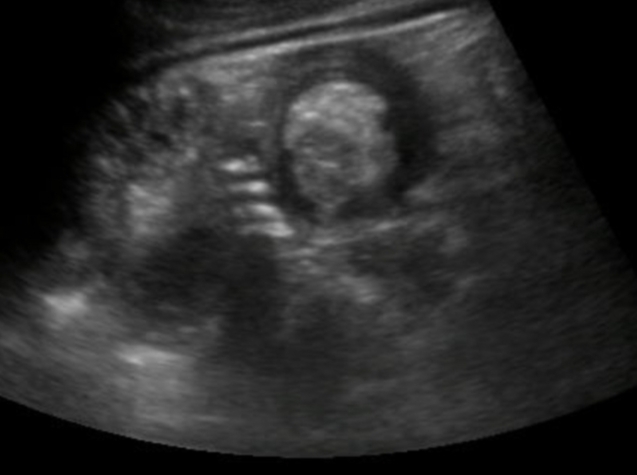

A 35-year-old female with a history of right nephrectomy and cholecystectomy presented with complaints of abdominal pain for one month. This was followed by anorexia, vomiting after food intake, weight loss for 10 days, and constipation for 3 days. On general physical examination, the patient appeared pale. Abdominal examination revealed tense abdomen, generalized tenderness, and sluggish bowel sounds. The results of the remaining physical examination were unremarkable. CBC showed 9.8 Hb. Serum electrolytes revealed hypokalemia at 3.7 and was replaced with potassium infusion. ECG showed normal sinus rhythm with no acute ST or T-wave abnormalities. An X-ray of the abdomen in the erect and supine positions revealed dilated bowel loops. Abdominal ultrasonography revealed a classic target sign or the doughnut sign (Figure 1). Surgery was planned and the patient underwent exploratory laparotomy with limited right hemicolectomy and ileostomy. Pathology of the resected bowel segment revealed granulomas with caseating necrosis, Langerhans giant cells, and epithelioid cells, indicating intestinal tuberculosis (Figure 2). The patient remained stable after surgery and was kept under observation for three days. She was discharged on anti-tuberculosis therapy with isoniazid (INH), rifampicin, ethambutol, and pyrazinamide for two months, followed by INH and rifampicin for the next four months.

Figure 1

Figure 1. Ultrasound abdomen showing target sign/donut sign in intussusception.

Ultrasound can usually diagnose intussusception with 100% accuracy by experienced radiologists, and is ordered as the first imaging modality. Ultrasonography of our patient revealed the typical Target Sign or Doughnut Sign, representing the oedematous external ring of intussuscipiens around a central intussusceptum (Figure 1). Other imaging modalities include abdominal computed tomography and colonoscopy.[13] Furthermore, the management of adult intussusception involves exploratory laparotomy or laparoscopy, followed by resection of the lead-point masses or areas of ischemia. In patients older than 60 years of age, appropriate oncologic principles followed by bowel resection are recommended, given the high incidence of malignancy.[14] Treatment by contrast or air insufflation is the treatment of choice in the paediatric population, but it is not used in adults. The disease should be treated by manual reduction before resection; however, preoperative biopsy should be performed in cases of multiple intussusceptions.[15]